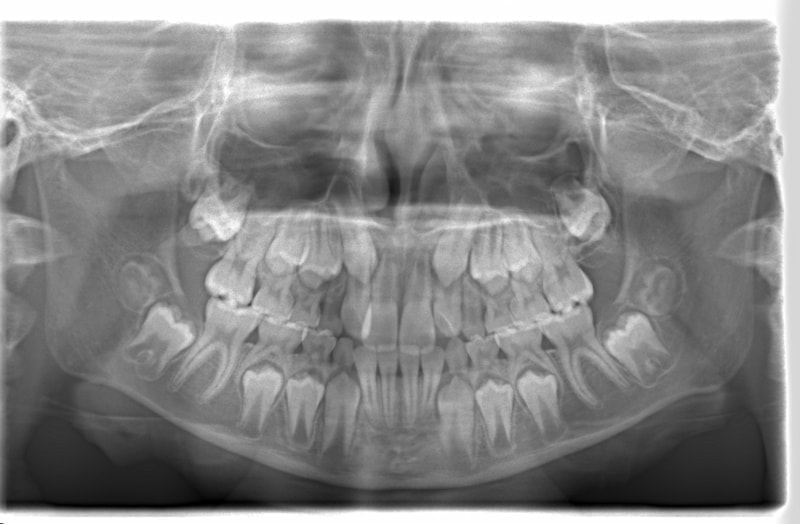

FX(フェイシャルアキシス)は85度なので東洋人の平均値に近く、下顎が前方に過剰成長するリスクは強くはありません。

しかしやはり上顎は劣成長で、下顎が優位な状態ではあります。

上下顎のギャップはありますが、顔面自体の幅径は良好な値を示していますので、スペース不足は拡大することによって解決できポテンシャルはあると考えられます。

左右の非対称もさほど強くありません。

骨年齢は実年齢よりも低めなので、今後下顎の旺盛な成長が見込まれます。

検査時のレントゲン分析では、上下顎の関係は、上顎の劣成長があり下顎前突傾向という値がでておりましたが、前歯ジャンプ後はフェイスマスクの効果もあり、上下顎の関係は正常化しています。